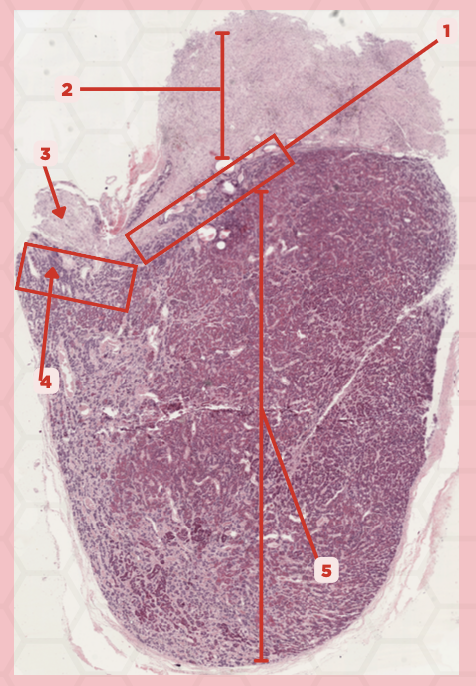

Pituitary

Identify the specimen.

Anterior Lobe

Identify the structure labeled as 1.

Posterior Lobe

Identify the structure labeled as 2.

Intermediate Lobe

Identify the structure labeled as 3.

Pars Tuberalis

Identify the structure labeled as 4.

Pituitary Stalk

Identify the structure labeled as 5.